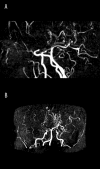

Moyamoya disease is a progressive vasculopathy leading to stenosis of the main intracranial arteries. The incidence of moyamoya disease is high in Asian countries; in Europe and North America, the prevalence of the disease is considerably lower. Clinically, the disease may be of ischaemic, haemorrhagic and epileptic type. Cognitive dysfunction and behavioral disturbance are atypical symptoms of moyamoya disease.Characteristic angiographic features of the disease include stenosis or occlusion of the arteries of the circle of Willis, as well as the development of collateral vasculature. Currently, magnetic resonance angiography and CT angiography with multi-row systems are the main imaging methods of diagnostics of the entire range of vascular changes in moyamoya disease.The most common surgical treatment combines the direct arterial anastomosis between the superficial temporal artery and middle cerebral, and the indirect synangiosis involving placement of vascularised tissue in the brain cortex, in order to promote neoangiogenesis. Due to progressive changes, correct and early diagnosis is of basic significance in selecting patients for surgery, which is the only effective treatment of the disease. An appropriate qualification to surgery should be based on a comprehensive angiographic and imaging evaluation of brain structures.Despite the rare occurrence of moyamoya disease in European population, it should be considered as one of causes of ischaemic or haemorrhagic strokes, especially in young patients.